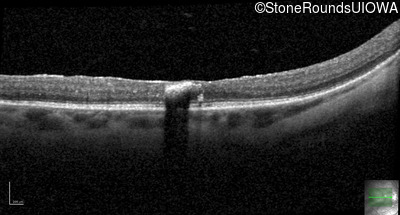

Age at visit: 50 years

Age at visit: 51 years